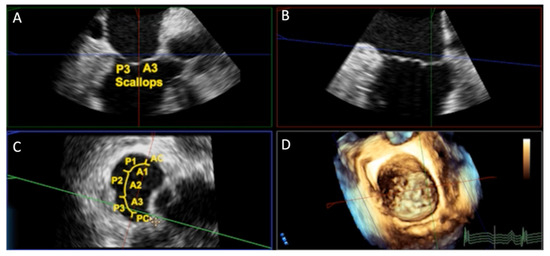

Review

Echocardiographic Assessment of Patients Undergoing Mitral Valve Repair

by Marco Rolando, Nadeem Elmasry, Federico Gobbi, Antonella Moreo, Nina Ajmone Marsan, Erberto Carluccio and Federico Fortuni

J. Cardiovasc. Dev. Dis. 2025, 12(12), 498; https://doi.org/10.3390/jcdd12120498 - 17 Dec 2025

Cited by 1 | Viewed by 1065

Mitral regurgitation (MR) is one of the most prevalent valvular disorders worldwide, with a growing burden driven by population aging and improved diagnostic capabilities. Understanding the mechanism of MR, whether primary, due to intrinsic valve abnormalities, or secondary, resulting from atrial or ventricular [...] Read more.

Mitral regurgitation (MR) is one of the most prevalent valvular disorders worldwide, with a growing burden driven by population aging and improved diagnostic capabilities. Understanding the mechanism of MR, whether primary, due to intrinsic valve abnormalities, or secondary, resulting from atrial or ventricular remodeling, is essential for optimal management. Echocardiography, particularly advanced modalities such as three-dimensional imaging and strain analysis, plays a central role in this process. It allows accurate quantification of MR severity, detailed characterization of valve and ventricular anatomy, and assessment of remodeling, all of which are critical for determining the optimal timing for intervention. Beyond diagnosis, echocardiography is indispensable in guiding therapy selection: it informs surgical planning by defining leaflet pathology for repair versus replacement strategies, and directs transcatheter interventions by guiding interatrial septal puncture, catheter orientation, and device deployment in real time. While surgery remains the gold standard for primary MR, transcatheter approaches including edge-to-edge repair and emerging mitral valve replacement are increasingly relevant, particularly in patients at high surgical risk or with complex anatomy. This review emphasizes the pivotal role of echocardiography in the pre-procedural assessment of MR, highlighting its ability to integrate anatomical, functional, and hemodynamic information to guide patient-tailored therapeutic strategies and optimize outcomes within a Heart Team framework. Full article

Show Figures

Figure 1